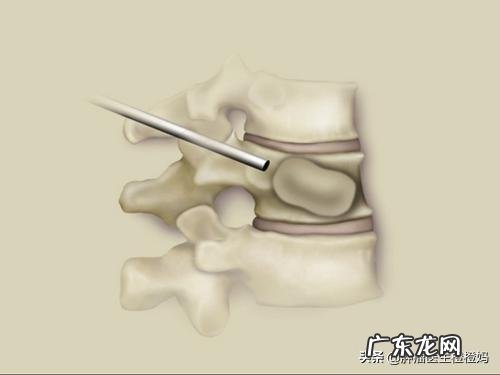

鼻咽癌最常见的骨转移部位为椎体转移,就是后背正中的骨头,患者常给我描述为“龙骨” 。骨转移初期往往没有任何症状,我之前就有病人定期复查时发现EBV-DNA明显偏高,达到50000多,胸腹部CT显示多发椎体转移,患者本人是没有任何异常表现的 。如果有症状了,最明显的表现就是骨痛,初期为隐痛,后逐渐加重,如果在椎体骨转移,弯腰活动时骨痛往往会加重 。(3)肺转移